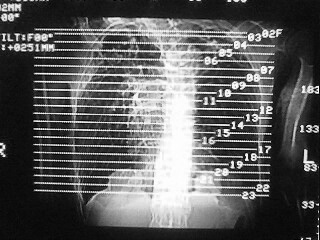

m,45,咳嗽、气憋月余。先天性畸形

1)两肺上叶继发性肺结核,部分肺间质纤维化。2)慢性支气管炎。3)肺气肿,两上肺多发性肺大泡。4)右侧胸膜增厚可能。5)脊柱上胸段畸形。

考虑:1)两肺上叶继发性肺结核,部分肺间质纤维化。2)慢支肺气肿并两上肺多发性肺大泡。3)右侧胸膜增厚可能。5)脊柱上胸段畸形。

补充一下,病人有强直性脊柱炎十多年

慢支炎、肺气肿、间质纤维化,双肺结核,脊柱侧弯

脊柱侧弯后突畸形,1)两肺上叶继发性肺结核,部分肺间质纤维化。2)慢支肺气肿并两上肺多发性肺大泡。3)右侧胸膜增厚可能。5